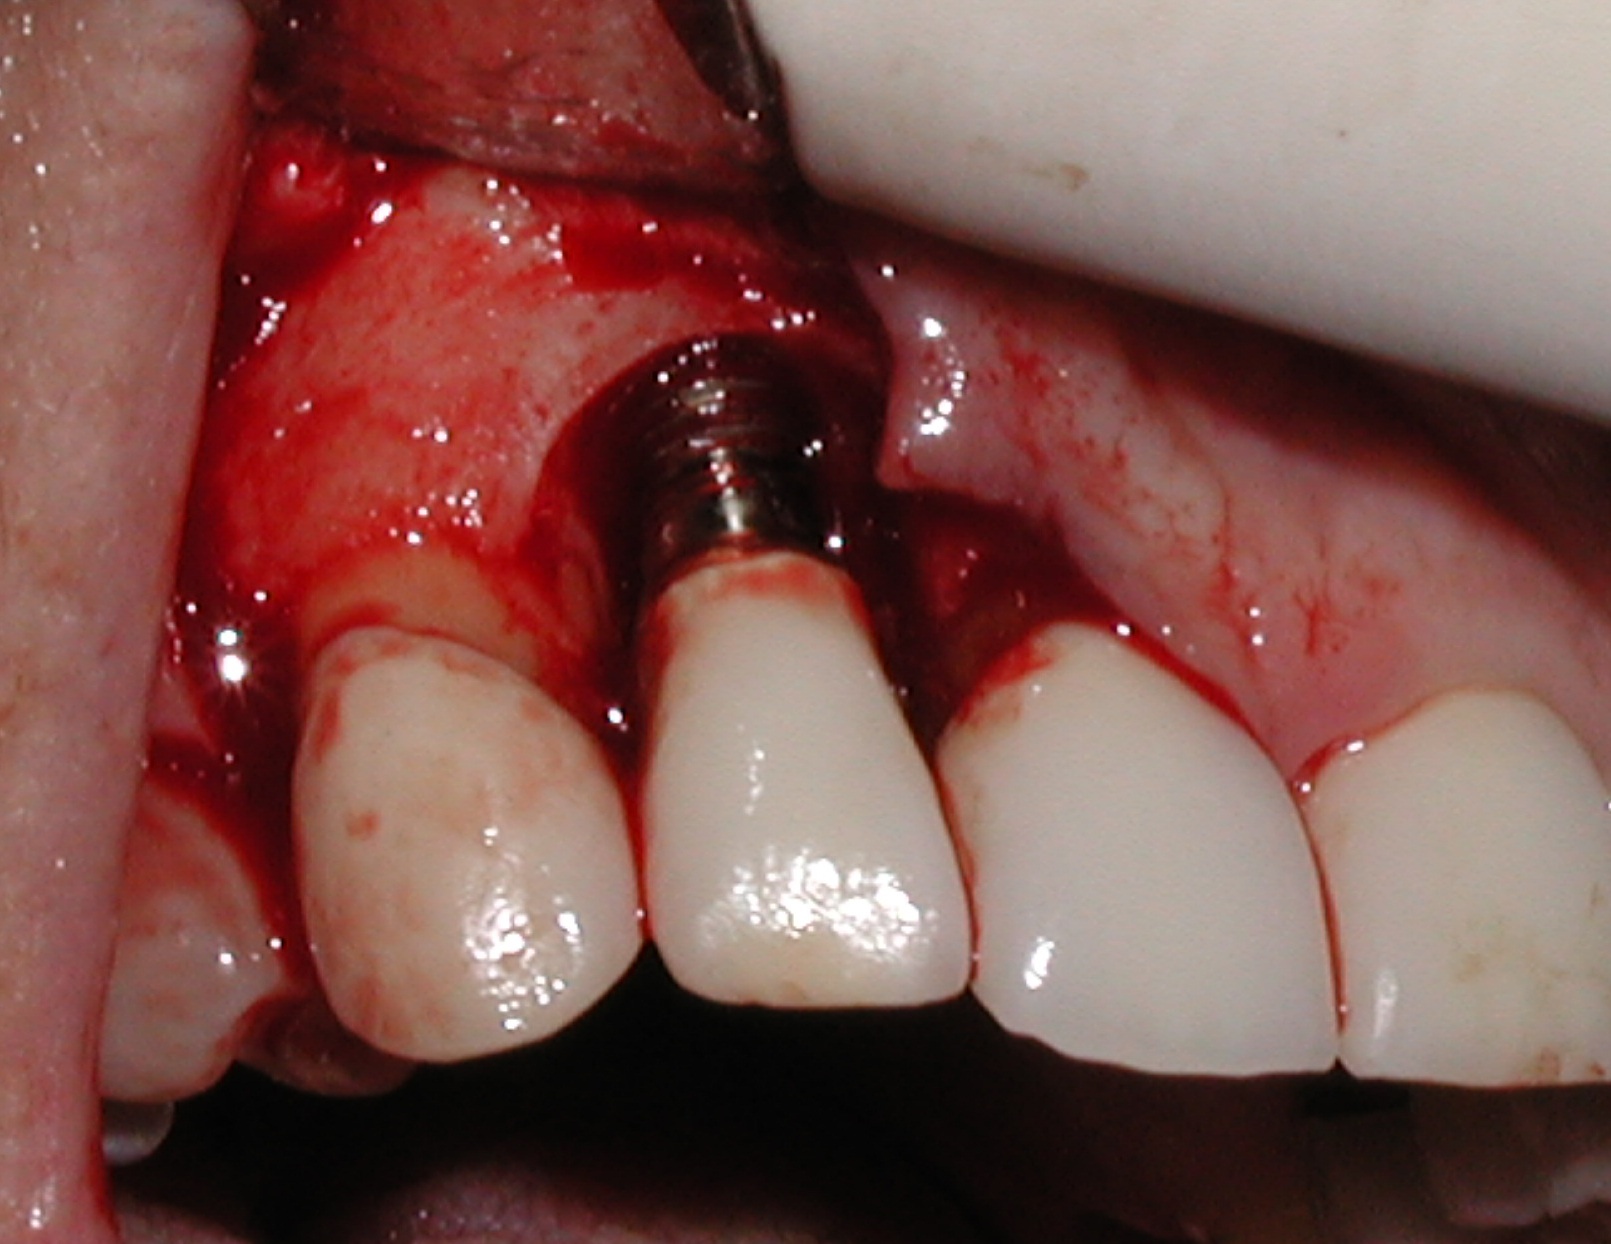

A guided bone regeneration (GBR) approach involving implant surface detoxification (Figure 2), placement of a bone graft combined with a barrier membrane (Figure 3 and Figure 4), and use of a systemic antibiotic has demonstrated the most predictable improvement in peri-implant parameters after destruction of supporting bone. GBR procedures demonstrated reductions in probing depth of 3.16 mm and 2.1 mm of radiographic bone fill in a recent systematic review and meta-analysis of 21 studies by Chan et al.21 Froum and Rosen22 defined a specific protocol based on reentry evaluation of previously treated peri-implantitis sites that included the use of rhPDGF-BB with freeze-dried mineralized bone and the addition of a resorbable membrane. Nonresorbable Gore-Tex® sutures were used to approximate the gingival tissue and were retained in place for 2 weeks. The patient was also kept on chlorhexidine for 2 weeks postoperatively. The reentry photographs from this report are quite impressive. However, the authors do caution the interpretation of re-osseointegration (Figure 5 and Figure 6).

Fig 2. Removal of cement and detoxification with tetracycline hydrochloride.

Figure 2